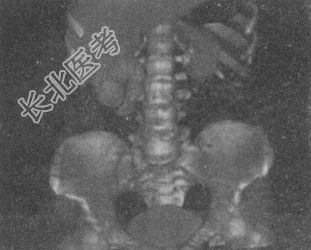

- 单项选择题女,42岁, 反复右下腹痛1个月,CT检查如图所示, 下列诊断正确的是

A、右侧输尿管上段结石,其上方输尿管扩张积水

B、右侧输尿管中段结石,其上方输尿管扩张积水

C、右侧输尿管下段结石,其上方输尿管扩张积水

D、右侧输尿管下段结核,其上方输尿管扩张积水

E、右侧输尿管下段炎性狭窄,其上方输尿管扩张积水